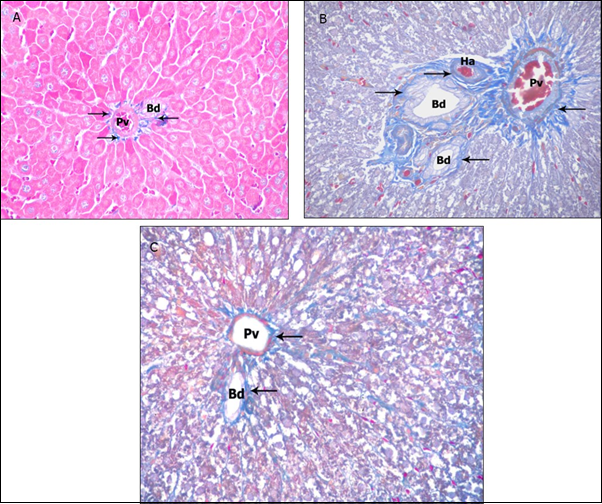

Masson’s trichrome-stained liver sections showed normal distribution of collagen fibers around the portal area in the 1st group (Figure 10a) and no difference could be detected in the 2nd group. In the 3rd group there was abundant increase in the amount of the blue-stained collagen fibers around the portal areas (Figure 10b). However, in the 4th group there was marked reduction in deposition of collagen fibers around the portal area compared to ZnONPs-treated group (Figure 10c).

Figure 10.Photomicrographs of sections in the liver: (a) Control group showing normal distribution of collagen fibers (arrow). (b) ZnONPs-treated group showing abundant stained collagen fibers surrounding the portal area. (c) ZnONPs &VE- treated group showing reduction of the collagen content in portal area. (Masson’s trichrome X 200)